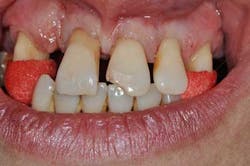

Figs. 3a, b, and c: Extraction of the upper incisors and maxillary removable acrylic placement

- Provisional acrylic removable partial denture placement after the extractions of the upper teeth. It serves as a functional and esthetic test for the rest of the treatment.